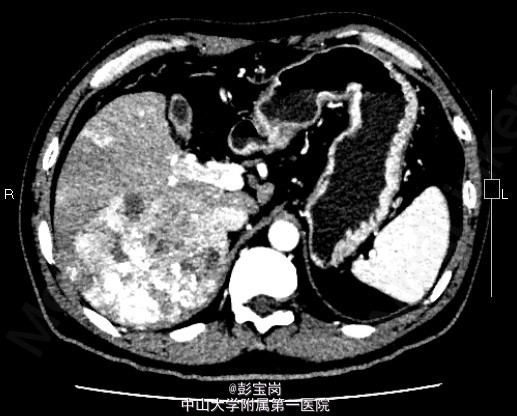

男性,42岁;因“肝癌行TACE术后,拟行手术治疗”入院。患者1月前体检发现原发性肝癌,于25天前在外院行肝动脉栓塞化疗(TACE)术。2天前患者就诊我院,查上腹CT示:右肝后叶多发结节或肿块,碘油栓塞后改变,病灶内和周边部仍有血供,门脉右后下支癌栓形成。现为进一步诊治门诊拟“肝细胞癌”收住我科。起病以来,精神食欲可,大小便通畅,体重无明显变化。既往史肾结石病史,否认肝炎病史。

查体无特殊; 检验:白细胞WBC:13.27;血红蛋白Hb:121g/L;血小板PLT:225x10^9/L;肿瘤标记物:甲胎蛋白(AFP)111.32 ug/L;癌胚抗原(CEA)9.40 ug/L;CA125 20.2 U/mL;CA19-9 11.04 U/L;HBsAg(+)

诊断:肝细胞癌 处理:右半肝切除术、胆囊切除术、腹腔粘连松解、膈肌部分切除修补、门静脉切除取癌栓、右侧肾上腺转移瘤切除